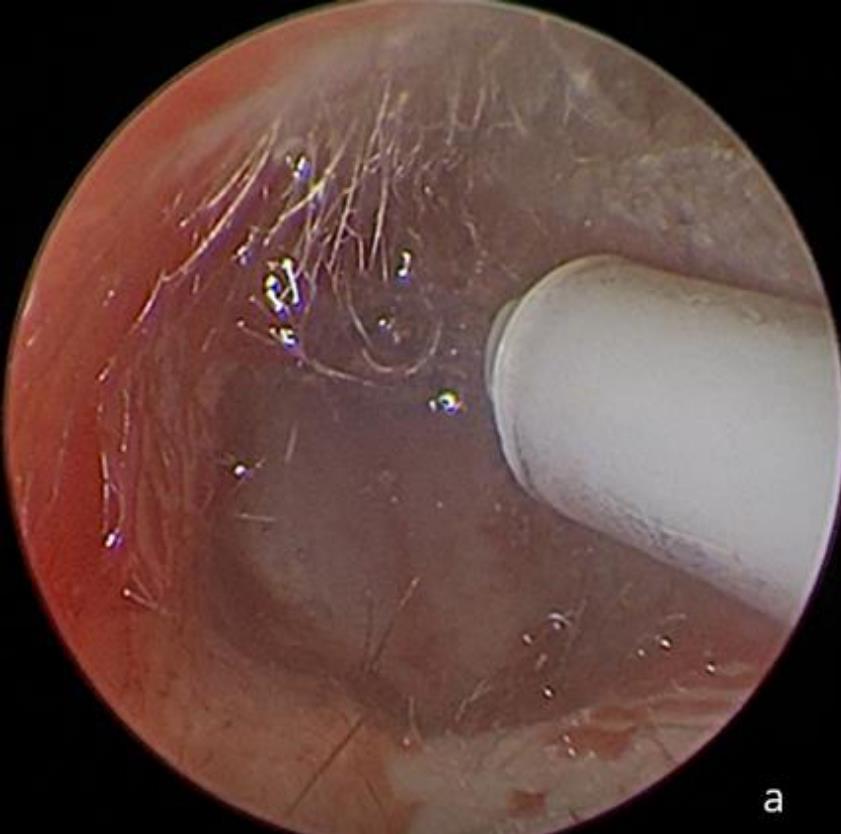

摘要:目的 探究一次性eyeMax洞察胰胆管成像系统辅助内镜逆行阑尾炎治疗术(ERAT)治疗阑尾炎的效果及安全性。方法 回顾性分析2023年4月-2024年9月在该院就诊,通过影像学或内镜检查确诊的54例非复杂性阑尾炎患者的临床资料。所有患者均行eyeMax洞察胆胰管成像系统辅助ERAT,于直视下观察阑尾腔,并通过冲洗、取石、扩张狭窄和支架引流等措施治疗阑尾炎。观察手术相关指标、术后疼痛程度、并发症发生情况、术后1年内复发率、结肠镜下表现、胰胆管成像系统下表现和胆胰管成像系统下治疗情况。结果 54例患者均顺利完成手术,技术成功率为100.0%,手术时间(60.6±27.9)min,住院时间(3.6±1.5)d;30例(55.6%)阑尾开口及周边黏膜充血水肿,2例(3.7%)可见脓液及污秽物流出;54例(100.0%)患者阑尾腔内壁充血水肿,51例(94.4%)可见腔内絮状物、脓液或脓苔附着,25例(46.3%)可见腔内粪石,15例(27.8%)可见管腔走形迂曲或狭窄。所有患者予以eyeMax洞察胰胆管成像系统治疗,简单灌洗54例,网篮取石20例,支架引流25例。术后VAS评分为0(0,0)分,明显低于术前的6(3,7)分,手术前后比较,差异有统计学意义(Z = -6.24,P = 0.000)。所有患者术后症状均暂时缓解,术中及术后未发生穿孔和大出血等严重不良事件。随访1年内,阑尾炎复发率为20.4%(11/54)。结论 EyeMax洞察胆胰管成像系统辅助ERAT是治疗非复杂性阑尾炎安全和有效的疗法,其具有直视下精准操作、保留阑尾功能、症状快速缓解、无X线暴露和精准诊疗阑尾病变等优势。值得应用于临床。